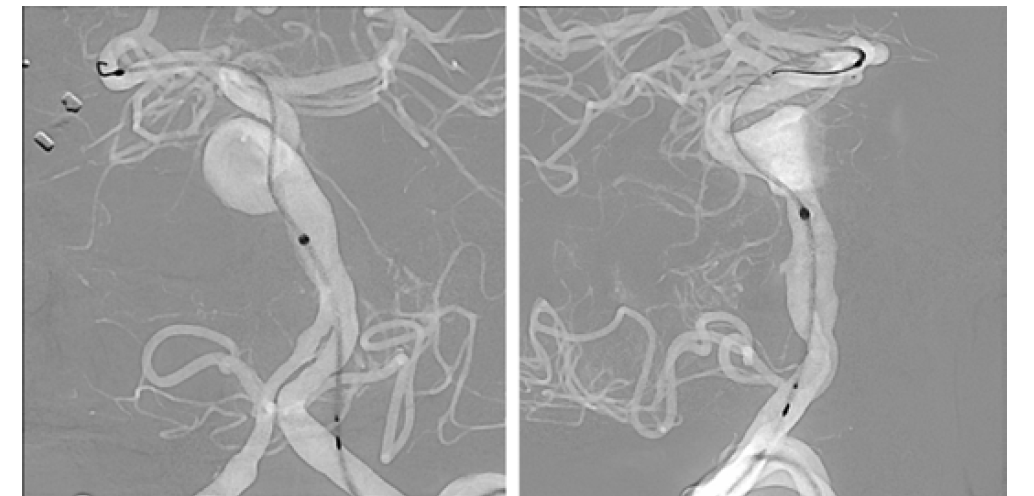

After a 3-stent construct was built, a DynaCT Micro with contrast was obtained, which demonstrated excellent stent-stent and stent-wall apposition (Figure 15). Even more important, it resolved an entire collateral arcade, replacing the native basilar artery and extending from the distal left vertebral artery (no stent covering the origin) to the distal basilar artery (1-stent coverage). This anatomic resolution enabled a more aggressive approach to the aneurysm neck, and ultimately 6 stents were placed. This anatomic collateral has previously been theorized and assumed to occur in the setting of giant midbasilar aneurysms without infarct. However, with DynaCT Micro, it can actually be visualized.

The original plan was to coil off the right vertebral artery distal to PICA. However, the imaging resolution of the ARTIS icono enabled visualization of critical medullary perforators distal to the PICA origin (Figure 16). The plan was therefore modified to coil off the vertebral distal to the most distal of these perforators. The distal right vertebral artery was successfully embolized distal to the perforators (Figure 17).

The patient returned for a 6-month follow-up angiography. Anterior-posterior, lateral, and 3D dual volume imaging was done at 6 months (Figure 18). Note the calcified shell of the aneurysm on the 3D image. The patient was neurologically normal and returned to work as well as running multiple times per week.